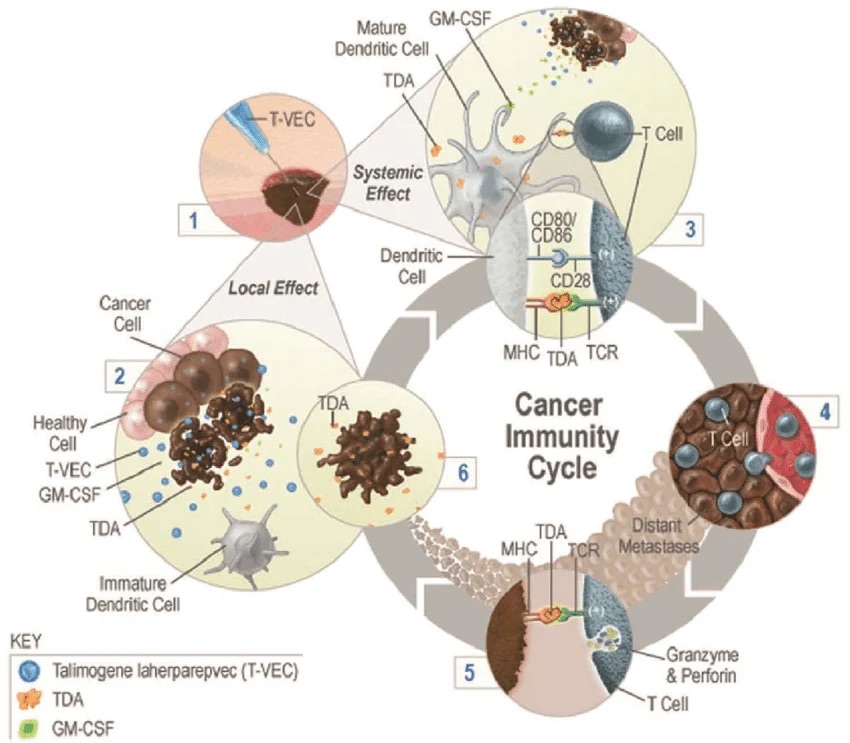

T-VEC Treatment for Melanoma: Harnessing a Virus to Fight Cancer

What are each of the doses of IpiNivo doing biologically?

Why do Oncologists only use 4 doses of IpiNivo in the treatment of Metastatic Melanoma?